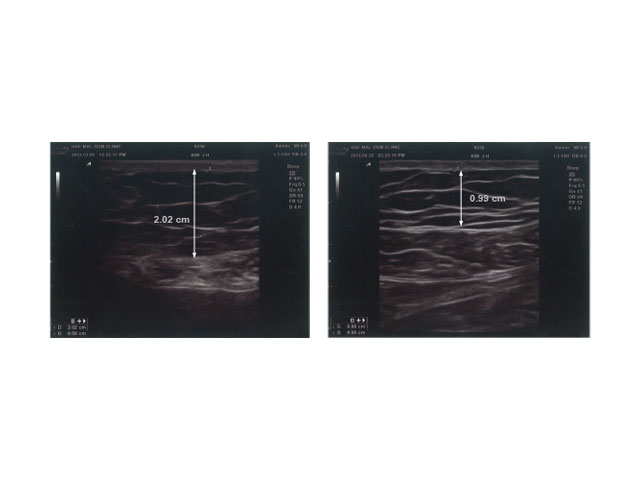

ANTES Y DESPUÉS

Con COOLshaping obtendrás los mejores resultados en tratamientos reductivos.

• Abdomen

Observaciones: Resultados 8 semanas después del primer tratamiento